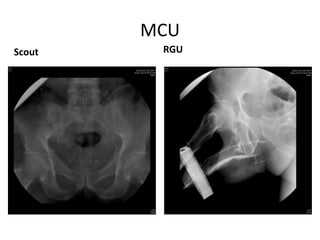

MCU

Scout RGU

RGU Full Bladder

Micturating Post void

• MCU report:-

• No strictures or leak